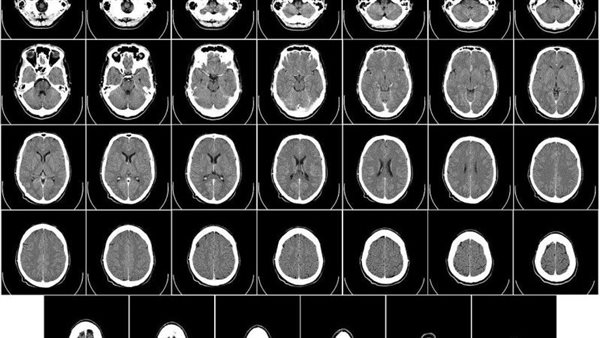

أظهرت فحوصات الدماغ بالرنين المغناطيسي لجميع المرضى الستة المسجلين في التجربة انخفاضًا سريعًا في الأورام خلال يوم أو يومين من العلاج.

وكانت تلك الاستراتيجية ناجحة، فقد أظهرت فحوصات التصوير بالرنين المغناطيسي التي تم إجراؤها بعد 24 و48 ساعة فقط من حقن علاج CAR T انكماشًا ملحوظًا في الأورام.